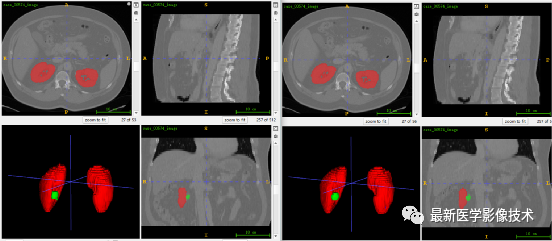

6、测试集分割结果、

左图是金标准结果,右图是预测结果。